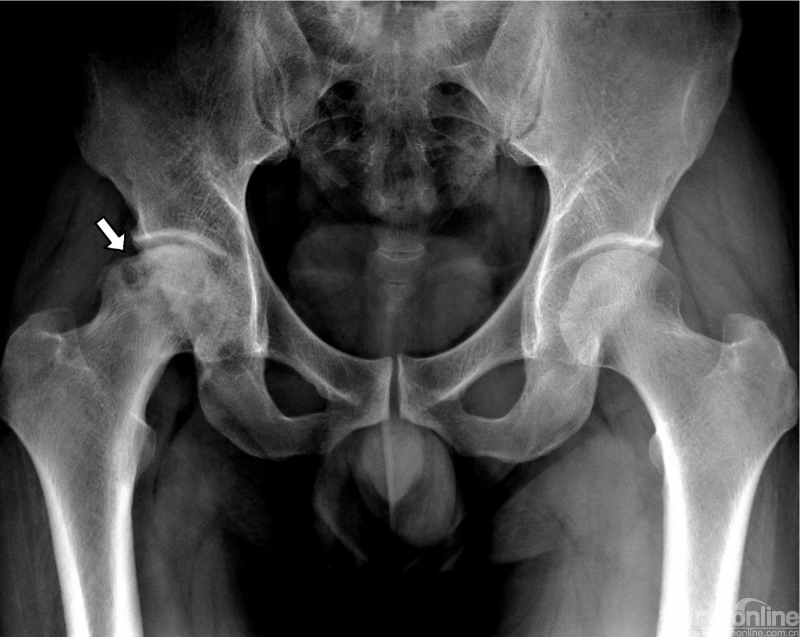

成人股骨头缺血坏死(中期)

右股骨头形态不规整,关节面不光滑,内部密度不均,可见片状增生硬化区及多个囊状透光区

股骨头内呈现混杂存在的致密硬化区、斑片状透光区和囊状透光区。部分承重区周围出现内外并行的透光带和硬化带。股骨头塌陷,表现为皮质成角、“台阶征”(股骨头皮质台阶样断开)和“双边征”(基底部外侧缘平行的双皮质影),但关节间隙正常。早期和中期还可见“新月征”(股骨头皮质下新月状透光影)和“裂隙征”(股骨头内裂隙样透亮线)。